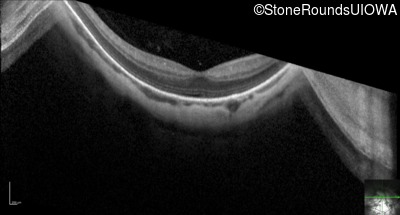

Optical Coherence Tomography - Left - 20/32

Exemplar / OCT Stack